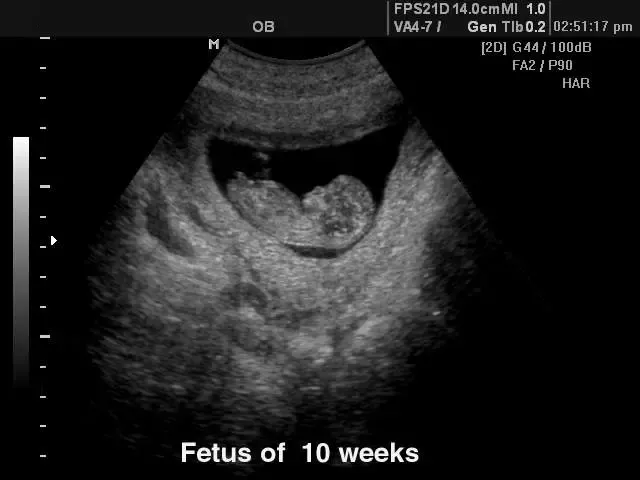

V naši ambulanti se predvsem trudimo, da bi imeli čimbolj profesionalen, diskreten in strokoven pristop k problematiki, ki jo obravnavamo. Da pa bi našim pacientkam zagotovili le najboljše, se nenehno izobražujemo in skušamo dosledno slediti sodobnim smernicam, ki se izoblikujejo tako pri nas kot tudi v tujini. Zato je med drugim na voljo tudi 3d 4D UZ - oziroma ultrazvočni pregled ploda.

V sklopu svoje ambulante ponujamo ginekološko in porodniško dejavnost, poleg tega svojim pacientkam nudimo preglede dojk in različne oblike ultrazvoka. Samoplačniško izdelamo tudi 3D 4D UZ.